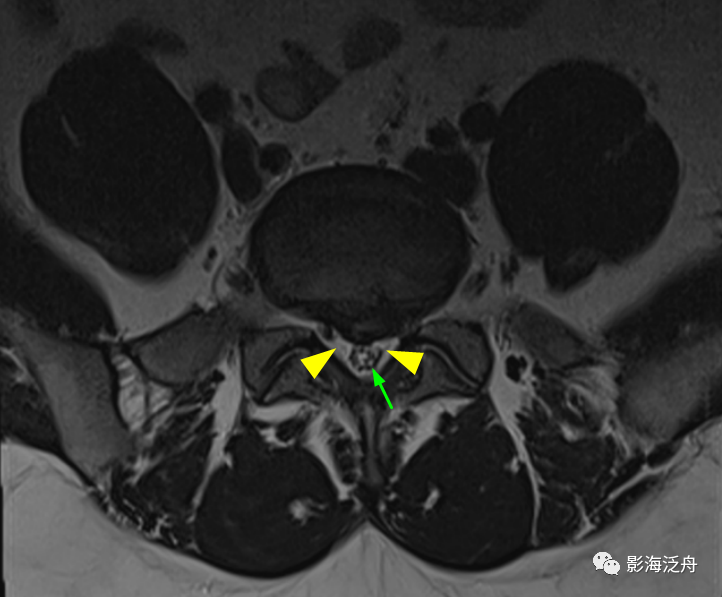

开篇那个患者的L5/S1水平横断面图像:可见椎管内大部分空间被脂肪组织占据(黄箭头),硬膜囊显著受压呈“V字”形改变(红箭头),硬膜囊内的马尾神经聚拢在一起显示不清。

病例二患者的L5/S1水平横断位像,可见椎管内硬膜囊外脂肪增多(黄箭头),硬膜囊受压,硬膜囊内的马尾神经呈聚拢改变(绿箭)。